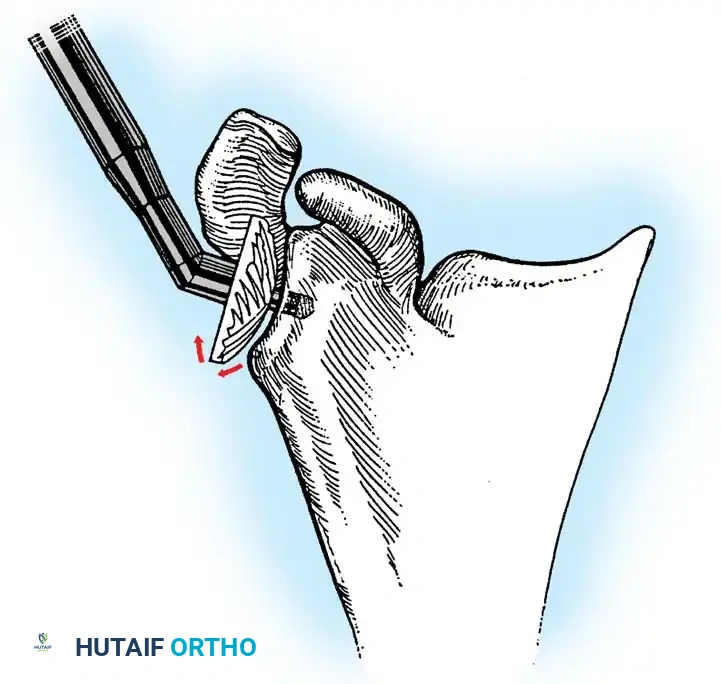

2. Joint Preparation

The tip of the olecranon is excised to facilitate access to the medullary canal. The distal humerus is prepared by resecting the trochlea and capitellum, preserving the epicondyles if possible to maintain collateral ligament attachments (though less critical in linked designs).

3. Canal Preparation and Implantation